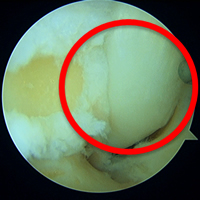

変形性足関節症は、足関節の表面に覆われている軟骨がすり減ってしまう疾患です。骨折や繰り返す捻挫など外傷によって起こることが多いと言われています。

歩行時に軟骨のすり減っている部分に疼痛が生じます。病態が進行すると、外観上も足の変形が認められます。

当院では、膝関節や股関節などの下肢全体のアライメントを含めて、痛みの原因を追究し、手術療法を決めるようにしています。従来は足関節前方を大きく切開して行う方法が行われていましたが、手術後の痛みや傷が大きくなることが問題でした。当院では患者さんへの侵襲を減らすため、皮膚切開を大きく行わない関節鏡視下関節固定術を積極的に導入しています。